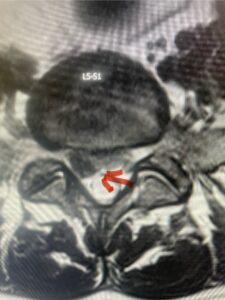

In this next case, this patient is a 47 year-old female who presents with intractable low back pain with severe pain, numbness, and weakness in the right lower extremity that had gotten progressively worse over a year. The patient had failed conservative management including physical therapy and epidurals. She was noted to have ⅘ weakness of plantar flexion. MRI demonstrated a large right L5-S1 disc herniation with severe compression of the descending right S1 nerve root (Fig 3). It was decided to perform a right L5-S1 hemilaminectomy for removal of the disc fragment and decompress the S1 nerve root. When you expose the disc, one must be certain to release any anterior adhesions to the nerve root in order to prevent a dural tear during retraction of the nerve root. It is also important to make sure during exposure and you finally encounter the dura after removing the ligamentum and fat, to make sure you are looking at the nerve root and not the main trunk of the thecal sac because if you don’t you can avulse or damage the nerve root if you retract the wrong structure.

Fig. 3a: Sagittal and axial T2-weighted lumbar MRI images demonstrating large right L5-S1 disc herniation (red arrows)

We found a massive subligamentous herniation which had to be revealed by having your partner retract the freed nerve root with a nerve root retractor and putting slight downward pressure on the more medial and anterior disc space. There is nothing more satisfying when the jelly (disc fragment) of the annulus (donut) comes squirting out and you remove a large chunk of disc material that clearly was stretching the ligament membrane and compressing the nerve root. This does cause back pain in addition to radiculopathy not only by the component of mechanical compression but also the stretching of the nerves within the ligament. We performed this surgery and noted that the nerve root was a very angry red color or hyperemic and we removed a large subligamentous fragment. The patient had improvement of her preoperative radicular symptoms.